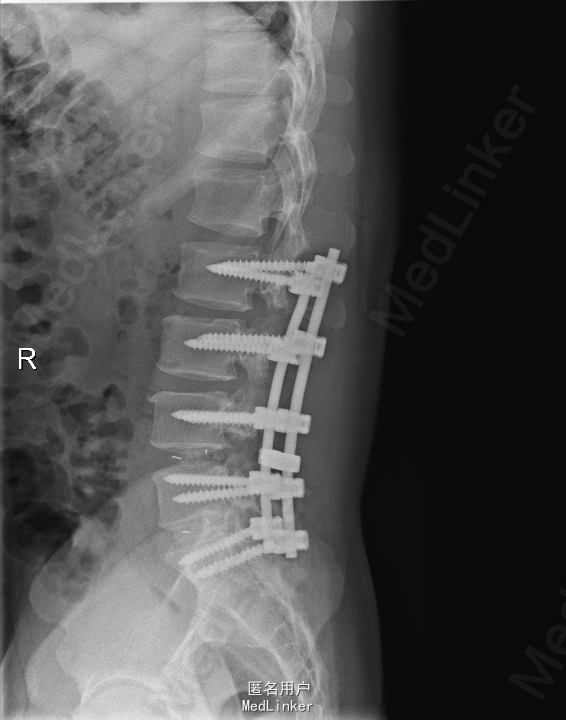

查体:腰部叩痛,腰部活动受限,左侧膝内侧、小腿外侧、内踝、足部感觉减退,右侧小腿、足背感觉减退,屈髋、伸膝、踝背伸肌肌力左侧4级,右侧4-5级,踇背伸、跖屈肌肌力左侧3-4级,右侧4级,双侧膝腱反射+,跟腱反射+,双侧巴氏征阴性,直腿抬高试验左侧40°阳性,右侧阴性。 辅助检查: X-ray:腰椎退行性变,多节段不稳 CT:腰椎间盘突出并椎管狭窄伴钙化,腰2-3,3-4,4-5,腰5骶1 MR:腰椎间盘突出并椎管狭窄,腰2-3,3-4,4-5,腰5骶1 上传受限无法全部上传,见谅

诊断:腰椎间盘突出症并椎管狭窄 处理: 1、完善相关辅助检查,明确诊断,有无手术指证; 2、完善手术评估,有无手术禁忌,手术风险及并发症; 3、在全麻下行腰椎后路多节段减压椎间植骨融合内固定术 4、腰2-3,腰3-4行开窗减压,腰4-5,腰5-骶1行椎间Cage植骨融合

随访: 1、应常规术后1个月、3个月、半年随访; 2、术后患者腰痛较前减轻,下肢麻木感觉较前好转,下肢活动较前有力,屈髋、伸膝、踝背伸肌肌力左侧4级,右侧4-5级,踇背伸、跖屈肌力左侧4级+,右侧4-5级,左侧肢体抬高试验阴性。 讨论: 1、多节段腰椎间盘突出,手术指证把握 2、责任节段的确立,以影像学间盘突出节段为依据,还是联系临床表现?还是术中探查为金标准? 3、多节段间盘突出,开窗髓核VS椎间植骨融合? 4、开窗髓核与椎间植骨融合相结合,如何确定融合节段与开窗节段? 5、多节段内固定,腰椎活动度影响,稳定与腰椎活动功能的平衡?